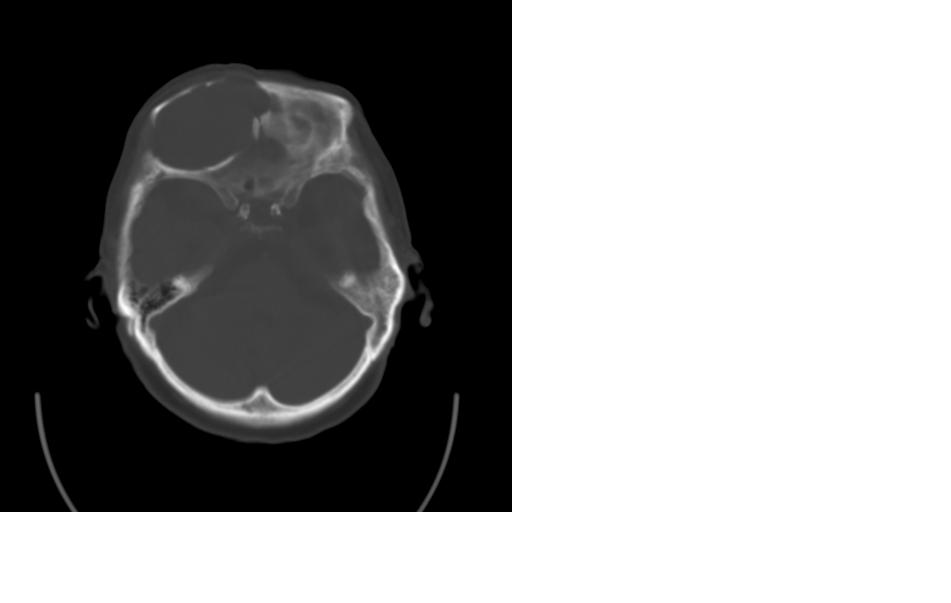

女,77岁,渐进性突眼2年,无其他明显症状

病变位于起源于右侧筛窦,右侧眼球受压移位,右侧大脑半球额叶白质受压塌陷,水肿不明显.额骨呈压迫性骨质吸收变薄.考虑脑膜瘤,建议增强吧

右侧额部软组织密度肿块,界限不清,明显向前下方增长,占位效应明显,内见钙化,局部颅骨明显吸收.考虑:右额叶脑膜瘤.建议:增强

右额窦粘液囊肿,向前累及筛窦并进入眼眶使眼球前突;向下进入颅内右额叶脑质及侧脑室受压

病变应起源于右侧额窦/或额骨板障,肿块周围骨包壳尚完整,呈膨胀挤压改变,右侧眼球受压移位,右侧大脑半球额叶白质受压塌陷,水肿不明显.考虑为良性病变,骨纤维瘤/或骨嗜酸性肉芽肿? 建议增强吧

支持:病变的起源我乐意定在右额窦。右额窦粘液囊肿或粘液腺癌累及筛窦、眼眶使眼球前突;向下进入颅内右额叶脑质及侧脑室受压变形。

右侧筛窦类圆形实质性肿块向颅内呈膨胀性生长,边缘较为光滑,其内似见囊性低密度影,边缘骨壁受压变薄移位,部分骨质缺损破坏

定位:来源右额窦。定性:良性占位—额窦黏液囊肿。理由1、病灶中心位于右额窦区,侵及筛窦并向下向前压迫眼球2、骨质呈膨胀性改变,骨质弓形变薄但骨壳完整,如为恶性骨质应为侵蚀性破坏3、黏液囊肿好发于筛窦、额窦。